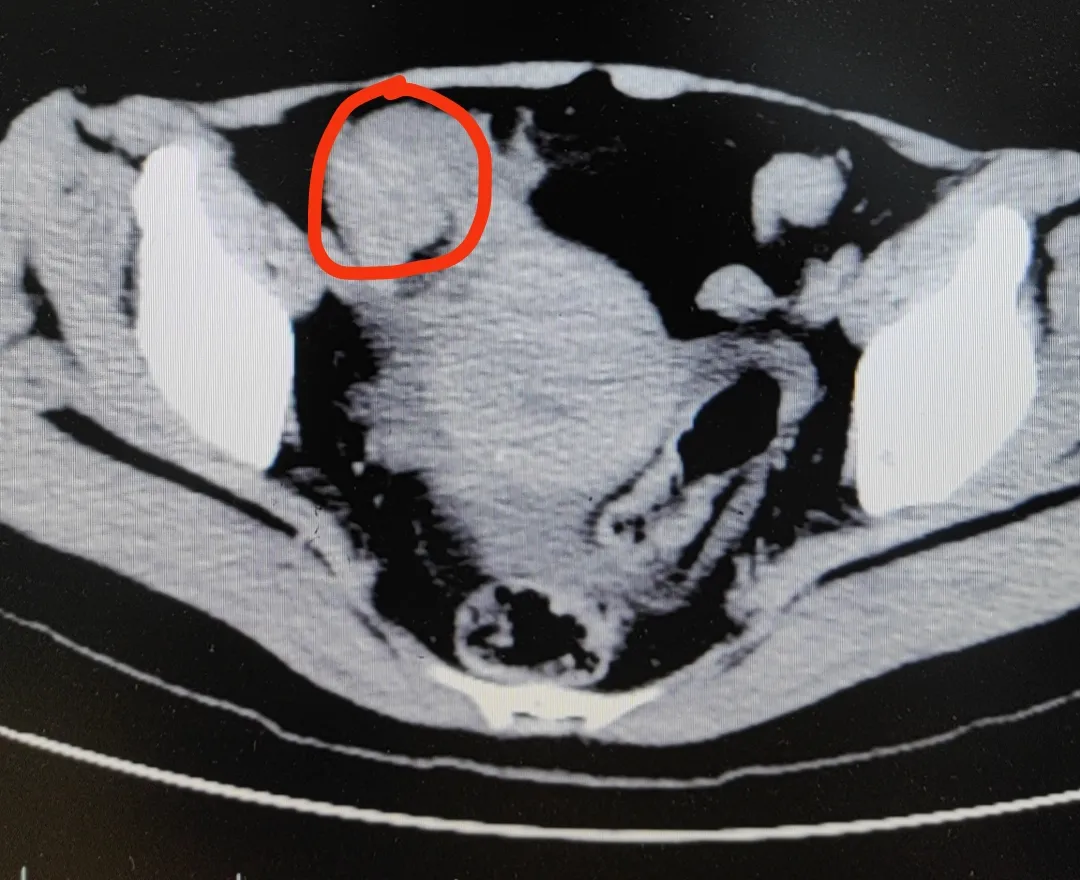

医生高度怀疑,冯女士发生了绞窄性肠梗阻。最后手术从肠子里切出一堆“石头”,也就是俗称的“柿石症”,最大的直径有4公分!